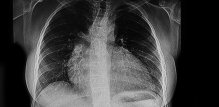

Uvećano srce (kardiomegalija) Budite prvi i komentirajte! 1 min čitanja Tomislav Stanić mag. educ. philol. croat. Tekst Dana Za vas izdvajamo Piše psihologinja Ljudi koji stalno kasne: Lijenost ili ozbiljan problem? Marija Šimunić 3 min čitanja Članak objavljen: 30-12-2025 Zatvori Podijelite članak Facebook Twitter Whatsapp Viber Kopirajte adresu